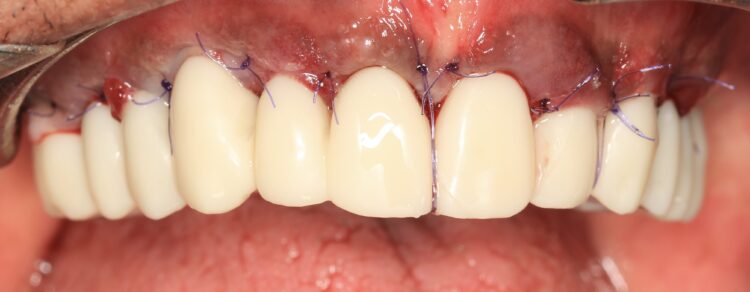

The finished and polished provisional restoration was screwed on the multiunit abutments at 15Ncm. The buccal flap was coronally advanced and closed with sling sutures using resorbable monofilament Glycolon 5/0 sutures.

This phase of treatment concluded with radiographs to confirm accurate implant placement. The patient was also given standard post-operative oral hygiene and care instructions. He reported no complications or concerns during the review appointment a week later.